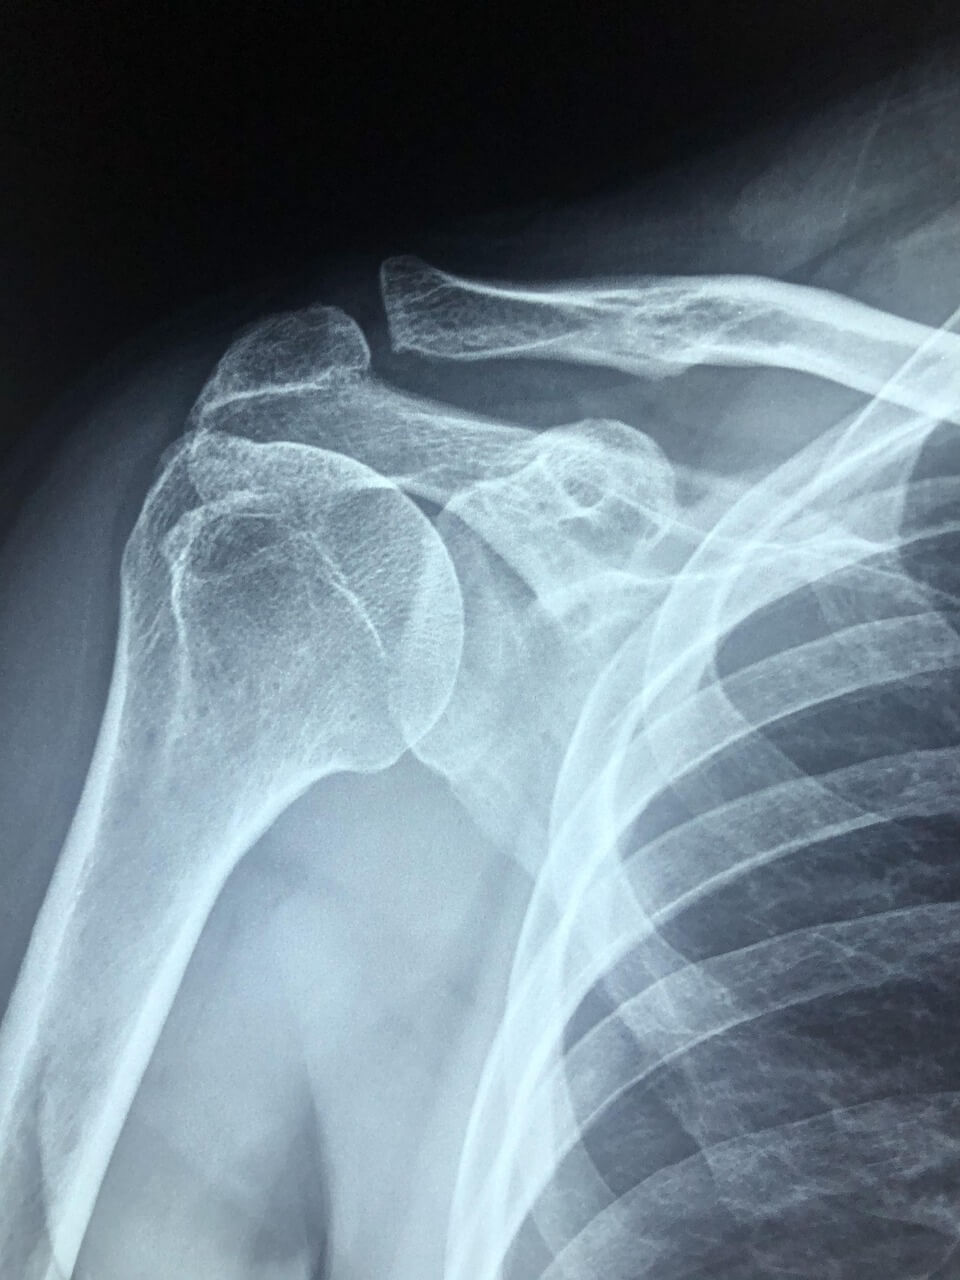

자가 진단은 참고용일 뿐, 정확한 판단은 영상 검사와 전문의 진료가 필수입니다.

| 스포츠 손상 | 회전근개 파열, 충돌증후군 | 팔 들 때 통증, 특정 각도에서 심한 통증 | MRI, 이학적 검사 | 물리치료, 주사치료, 수술 |

| 퇴행성 원인 | 오십견, 어깨 관절염 | 운동 제한, 지속적 통증 | X-ray, MRI | 약물, 물리치료, 관절 수술 |